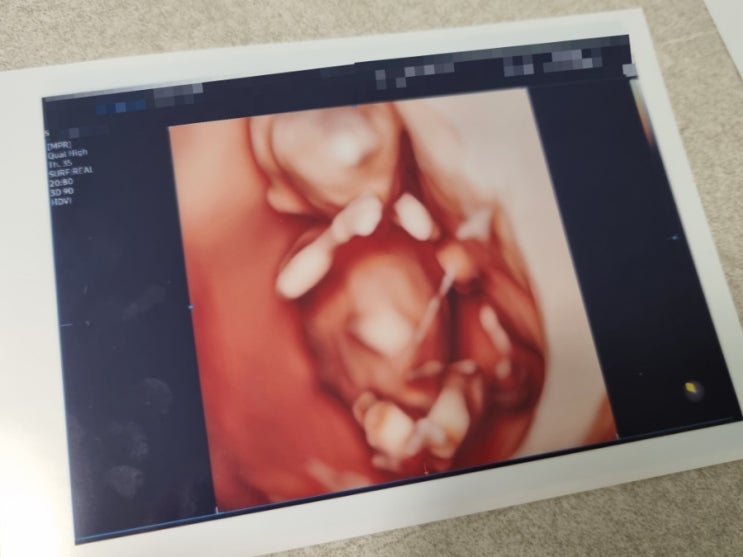

[임신일기] 임신 13~16주차 증상 / 16주차 성별 공개 / 2차 기형아검사 / 보건소 기형아쿠폰 분실 / 임산부 코로나 검사

임신 13주차, 14주차, 15주차 증상 - 두통 - 소화안됨 - 역류성식도염 - 가스 참 - 입덧이 더 심해짐 - 섬...

[임신일기] 임신 11주차~12주차 증상 / 정밀 초음파 / 1차 기형아검사 / 각도법 보는 법 / 비오템 튼살크림

임신 11주차~12주차 증상 - 두통 - 소화 안됨 (체덧?) - 턱 밑 뾰루지 - 배가 살짝 나오기 시작 - 비염 ㅠ ...